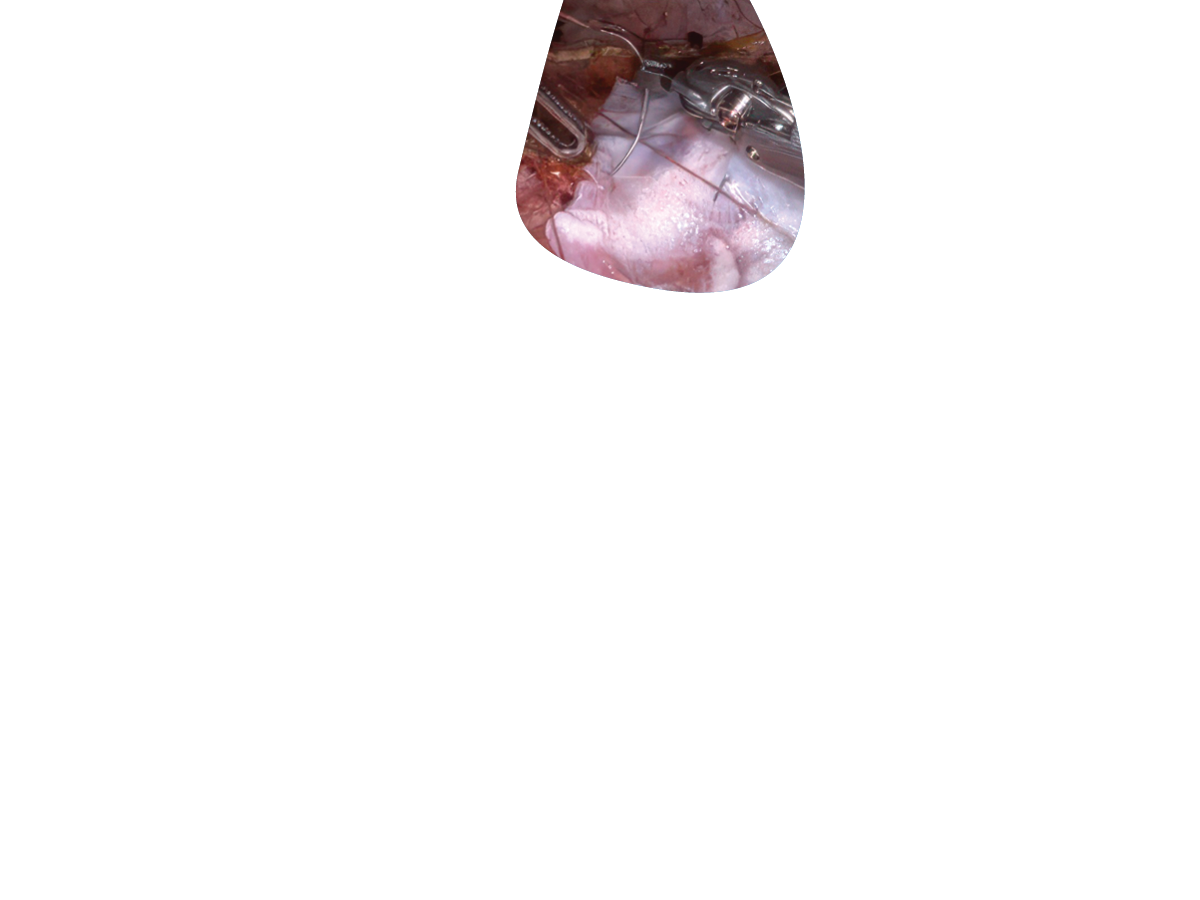

STRAVIX◊ PL

Lyopreserved Umbilical Tissue

STRAVIX PL Tissue was designed for the realities of today’s OR: fast-paced, high-stakes, and never one-size-fits-all. With high tensile strength2 and easy handling, it’s ideal for both compromised surgical sites and complex soft tissue management.

*Can be used as a wrap, cover, or barrier